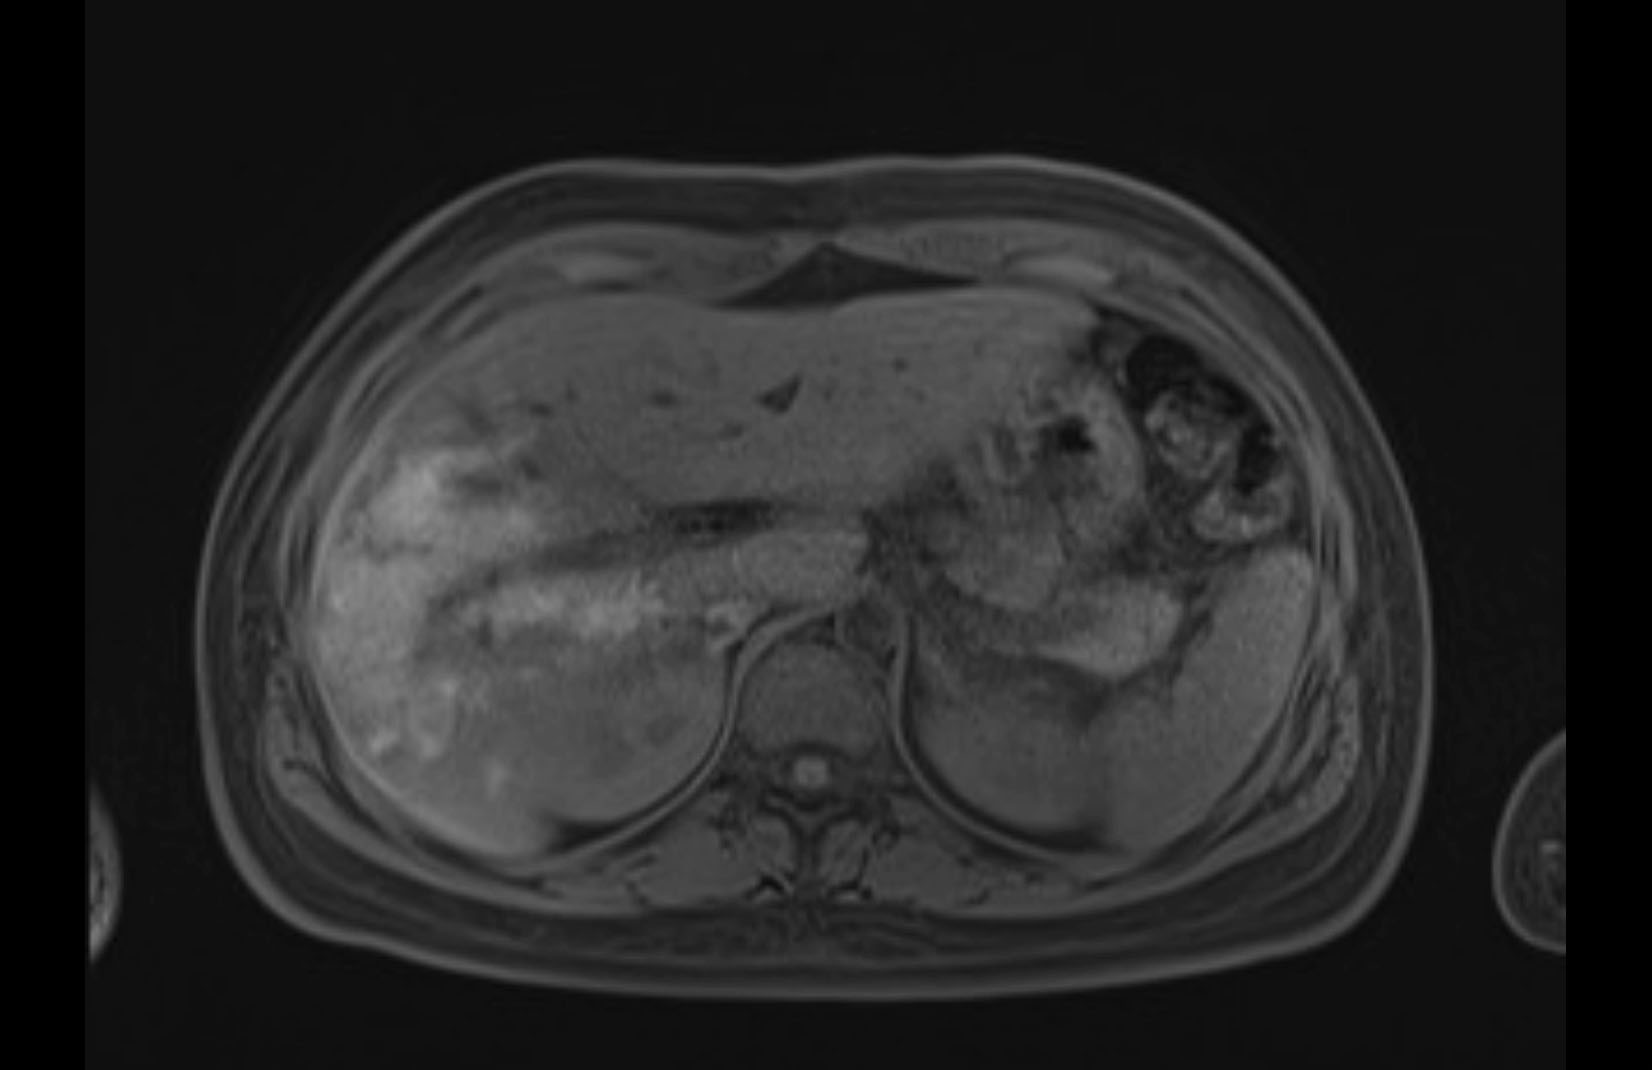

Imaging Analysis

Look through the patient's CT scan to identify any areas of concern for the necessary procedure.

MRI T1

Based on initial findings, which issue(s) would you be most concerned about?